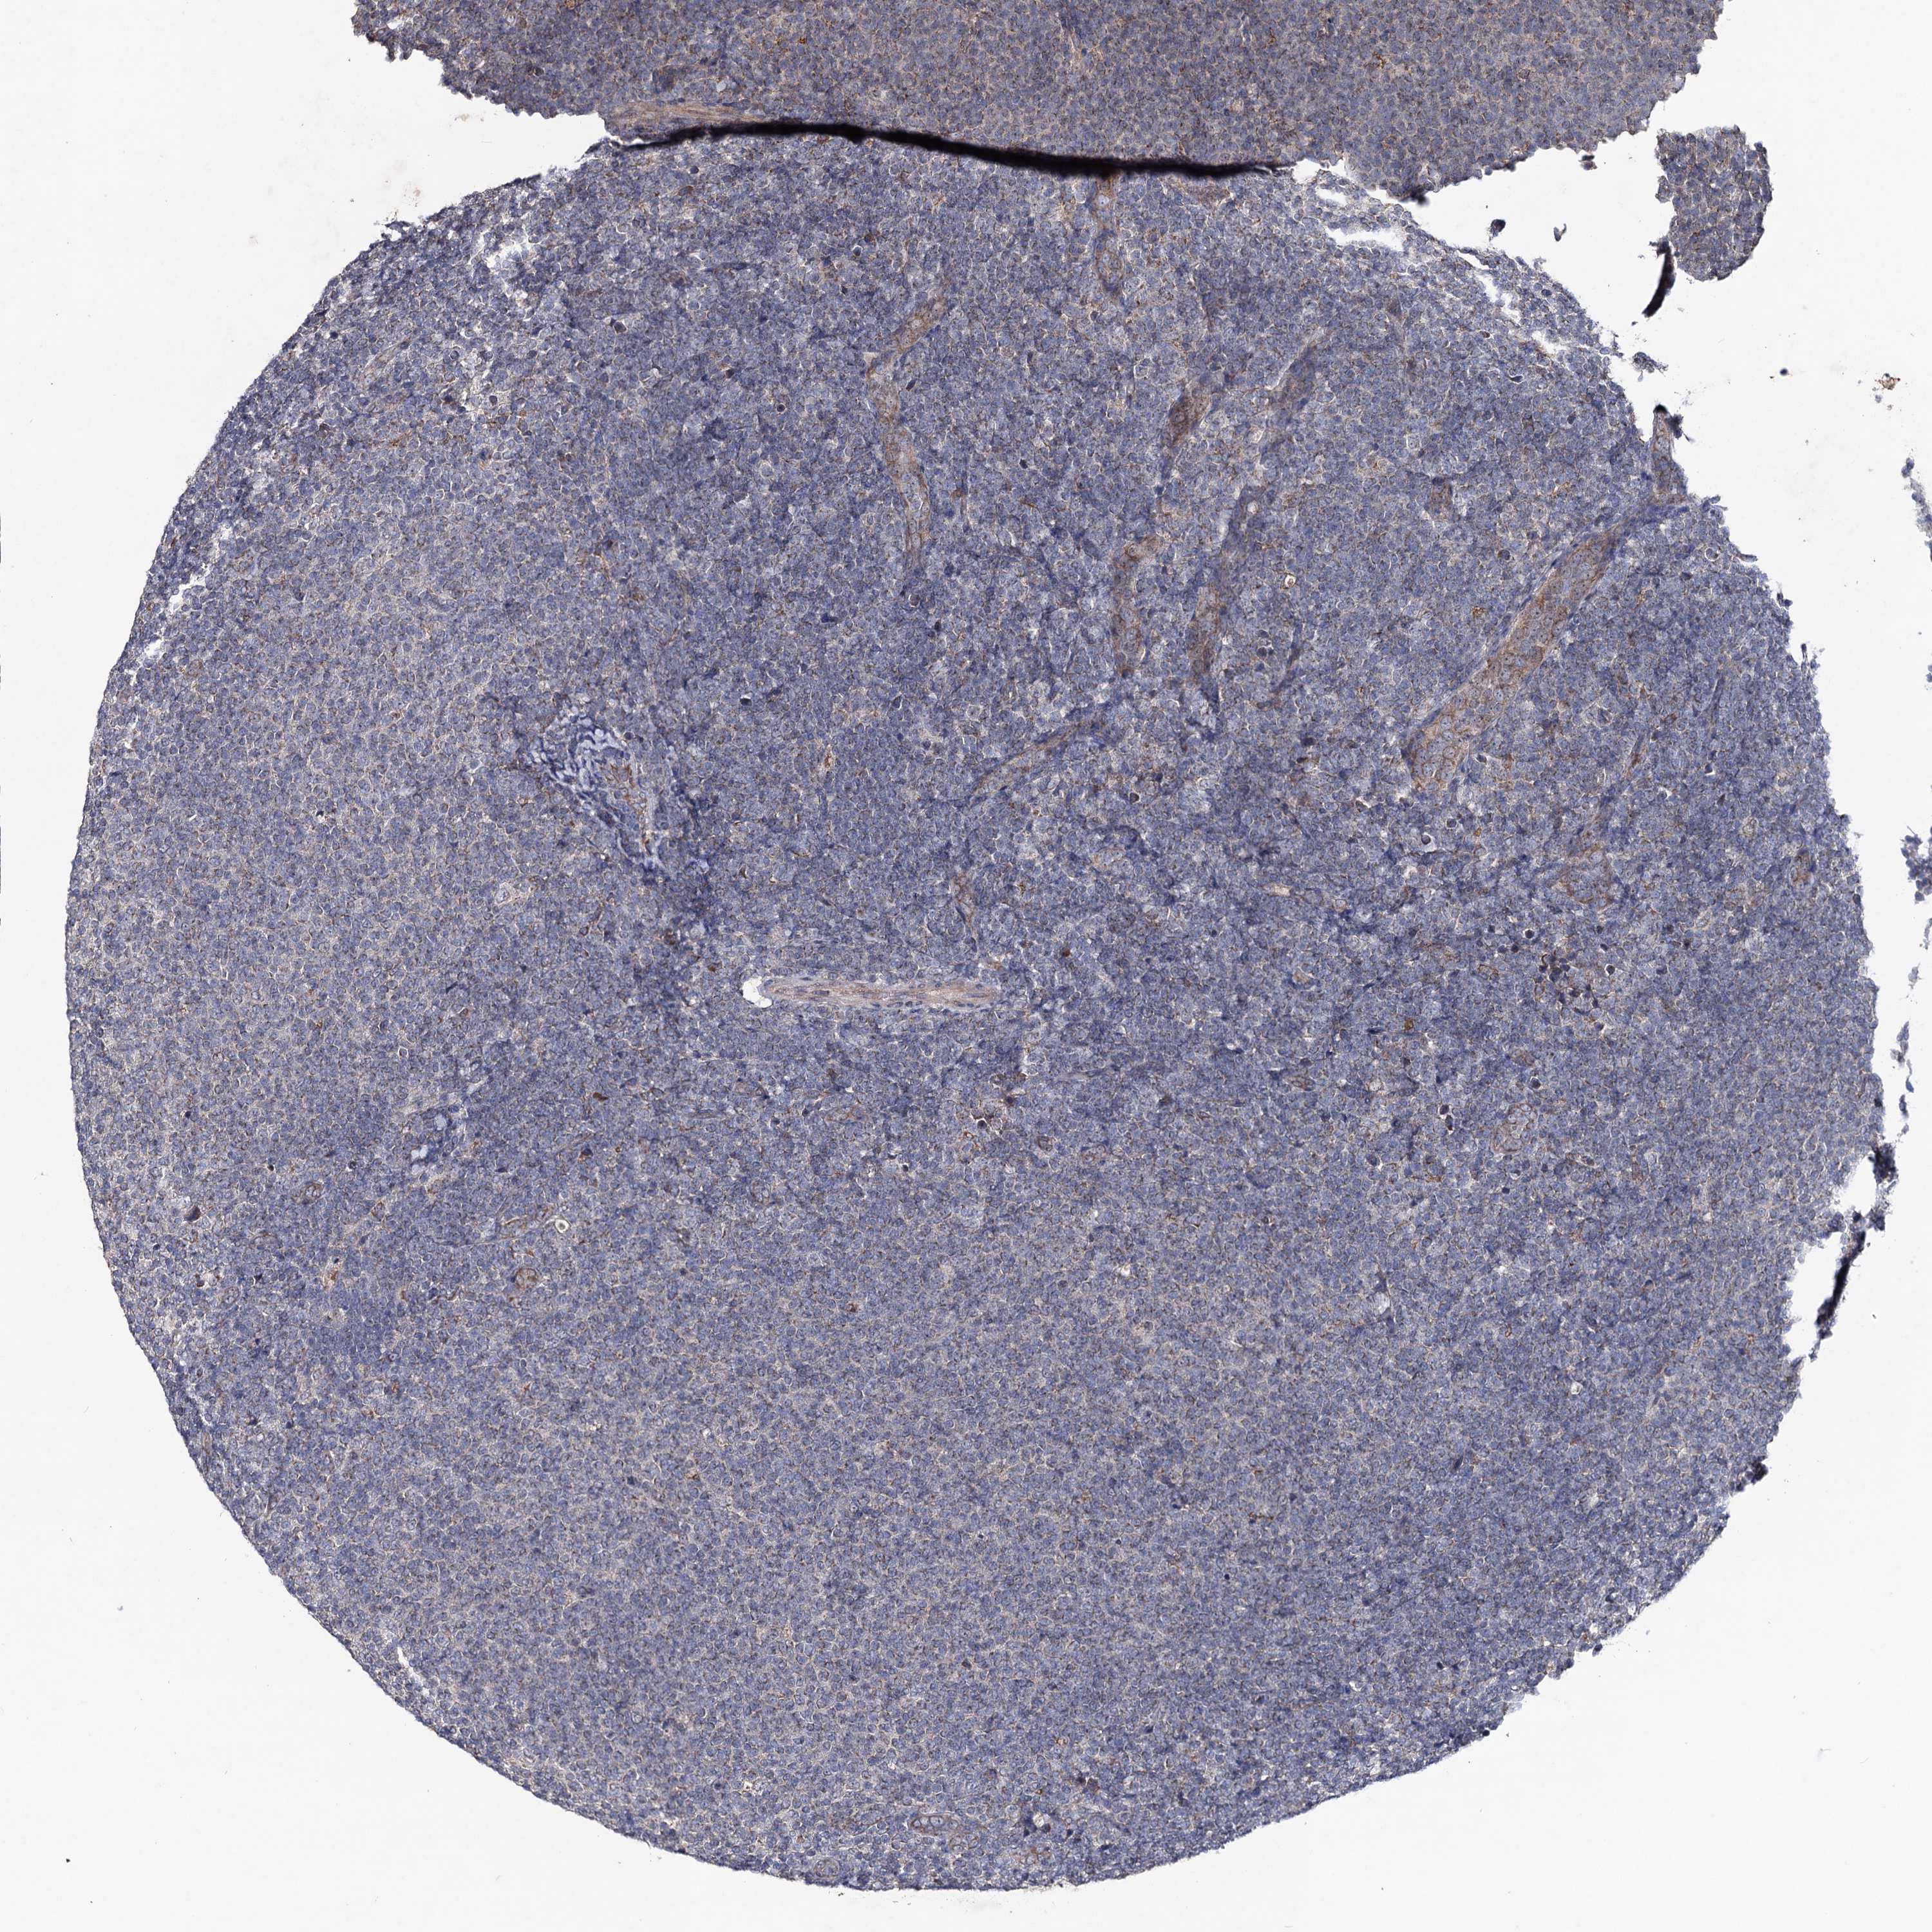

CANCER LYMPHOMA Show tissue menu

LYMPHOMA - Protein expressioni

A mouse-over function shows sample information and annotation data. Click on an image to view it in a full screen mode. Samples can be filtered based on level of antibody staining by selecting one or several of the following categories: high, medium, low and not detected. The assay and annotation is described here.

Antibody stainingi

Antibody staining in the annotated cell types in the current human tissue is reported as not detected, low, medium, or high, based on conventional immunohistochemistry profiling in selected tissues. This score is based on the combination of the staining intensity and fraction of stained cells.

Each image is clickable and will lead to virtual microscopy that enables deeper exploration of all samples and also displays staining intensity scores, fraction scores and subcellular localization as well as patient and tissue information for each sample.

Antibody HPA040978

Staining

High

Medium

Low

Not detected

Intensity

Strong

Moderate

Weak

Negative

Quantity

>75%

75%-25%

<25%

None

Location

Nuclear

Cytoplasmic/membranous

Cytoplasmic/membranous,nuclear

Hodgkin's disease, NOS

Malignant lymphoma, non-Hodgkin's type, High grade

Malignant lymphoma, non-Hodgkin's type, Low grade